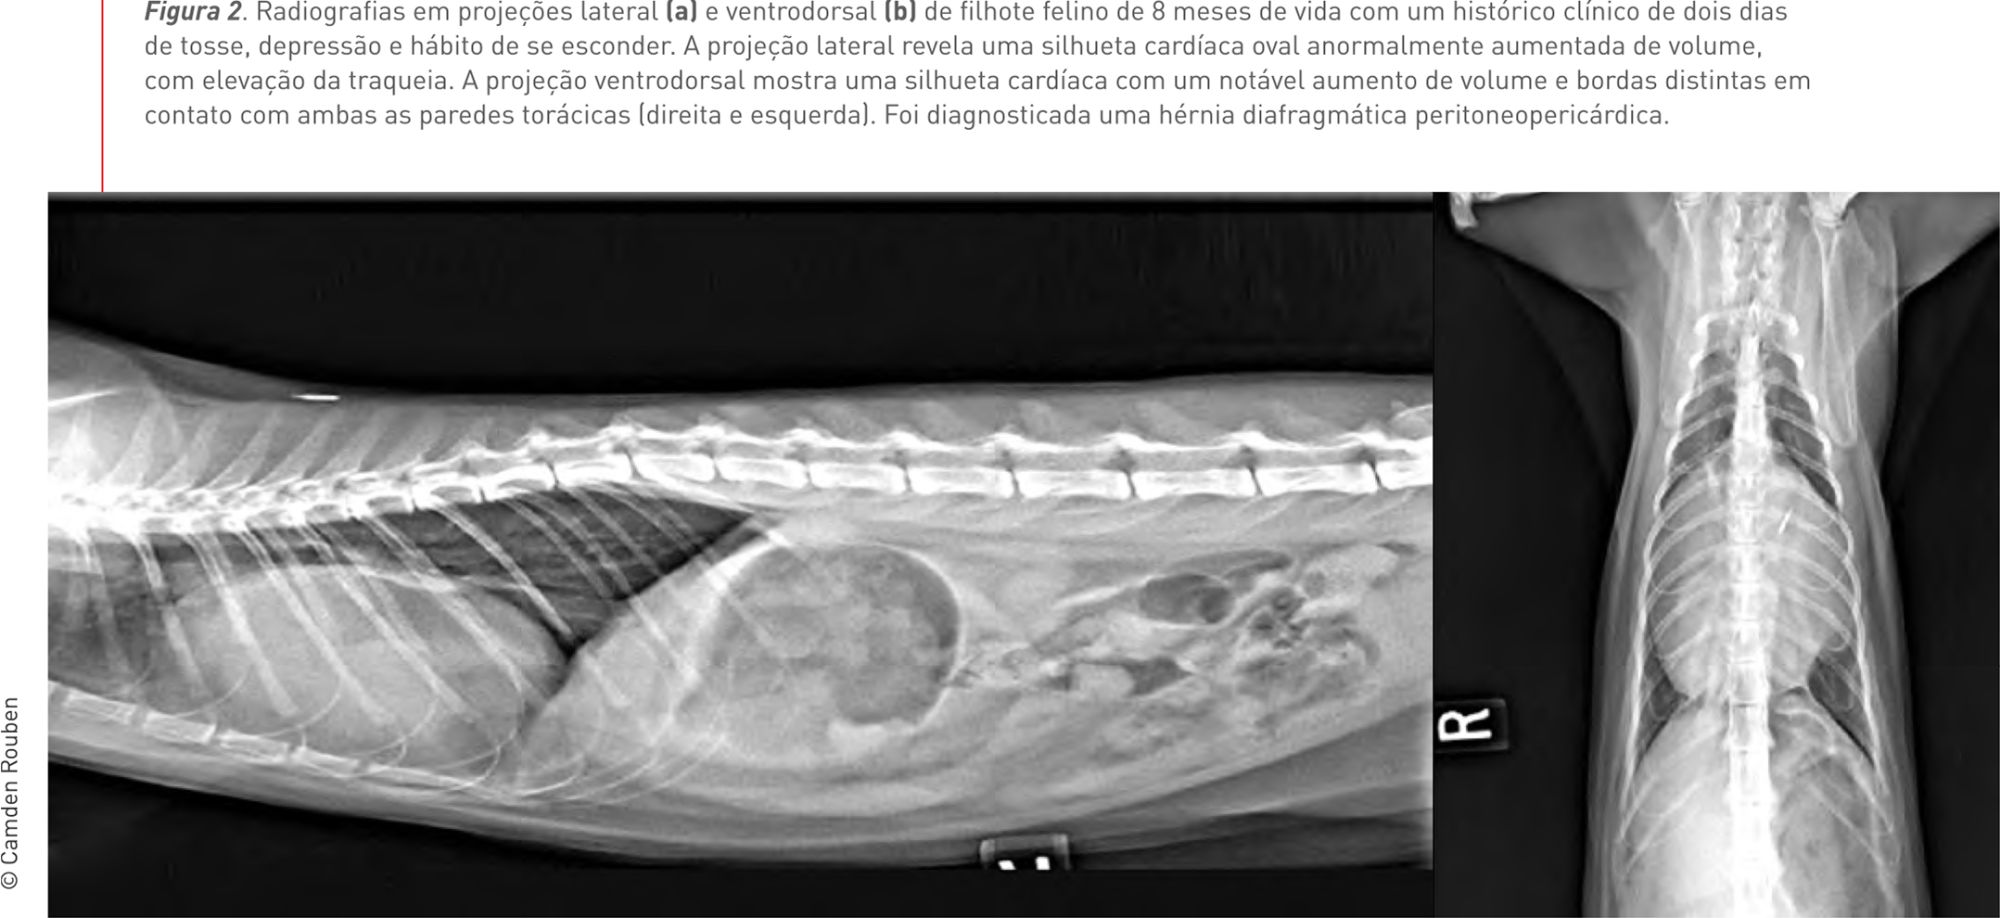

Figura 2. Radiografias em projeções lateral (a) e ventrodorsal (b) de filhote felino